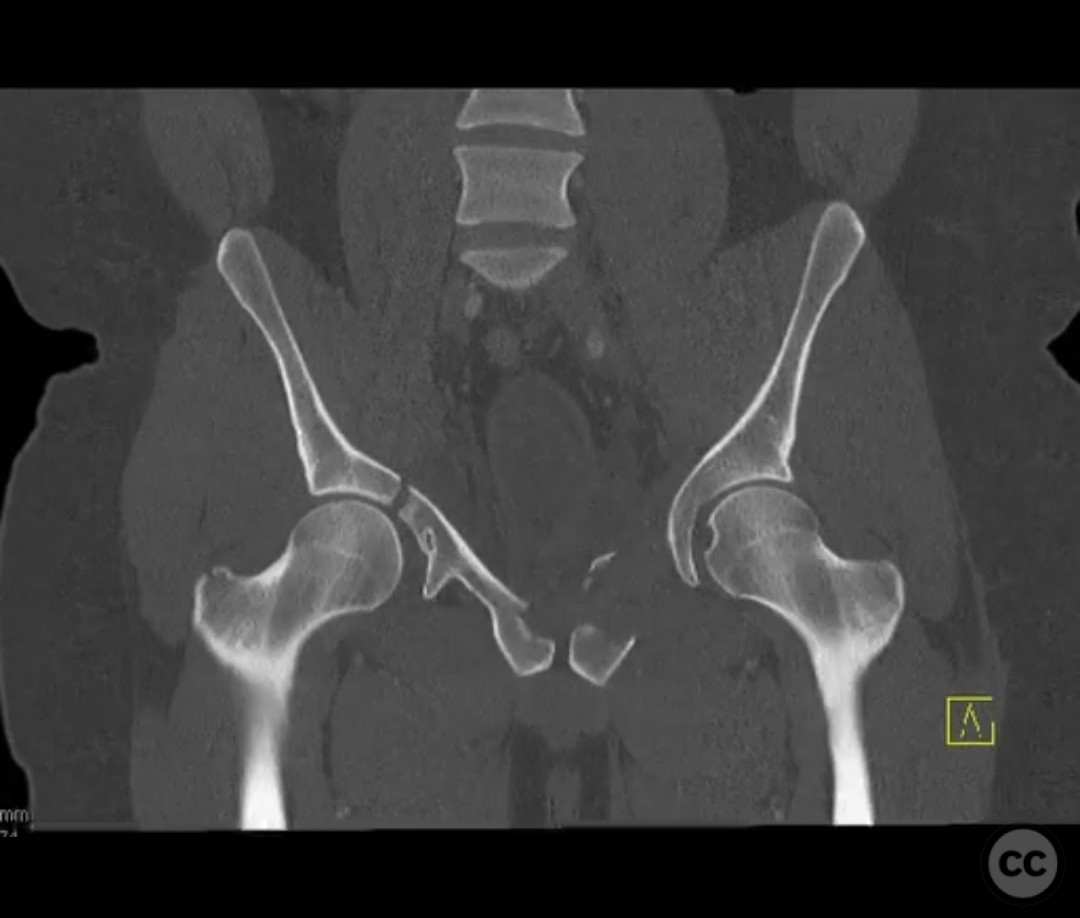

Clinical and radiological findings:  The patient presented with a highly unstable pelvic ring injury and a transverse acetabulum fracture, accompanied by a bladder injury. The bladder injury was addressed emergently with a low vertical midline Pfannenstiel incision for repair, followed by the placement of a low right-sided suprapubic catheter. Radiological imaging confirmed the transverse acetabular fracture and disruption of the left sacroiliac joint, along with a displaced sacral fracture.

Planning remarks:  The preoperative plan involved a staged approach to address the combined injuries. Initially, the focus was on stabilizing the pelvic ring to provide a stable base for subsequent acetabular reconstruction. The left sacroiliac joint disruption was to be reduced and stabilized first, followed by lag screw fixation of the displaced sacral fracture. Additional screws were planned as anatomical corridors allowed. An external fixator was considered to support the posterior ring stabilization. The second stage involved open reduction and internal fixation (ORIF) of the acetabulum through a Kocher-Langenbeck approach, with potential anterior column fixation via the modified Stoppa approach if necessary.